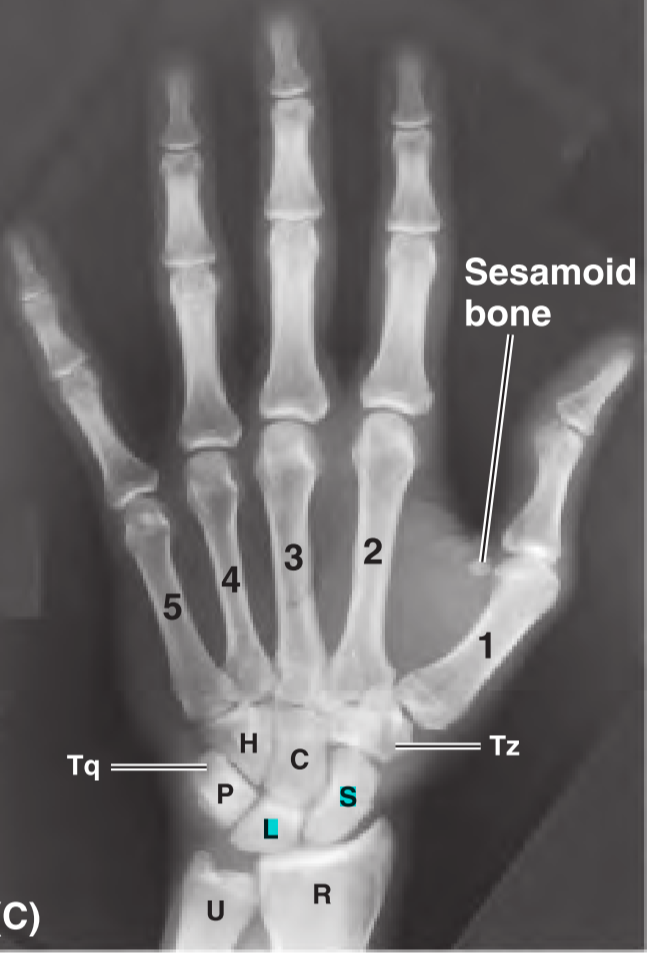

Identify the structures of the distal row of the wrist (A-D).

Identify the structures of the proximal row of the wrist (E-H).

Which carpal bones articulate with the radius at the wrist joint?

The scaphoid and lunate bones articulate with the radius at the wrist joint.